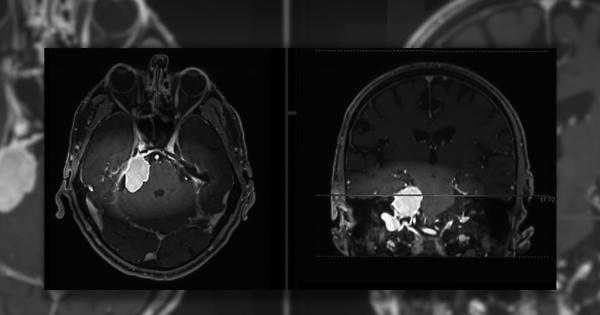

Meningiomi, i sintomi da tenere d'occhio